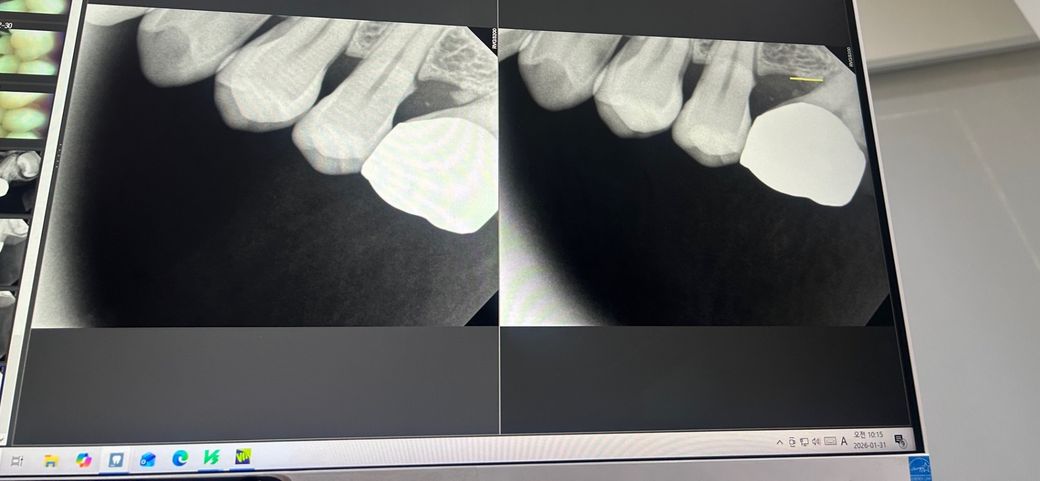

*사진첨부함

금니크라운과 그앞에 상실치아가 있었는데 (아래 기울어진거 보이시죠..) 잇몸사이에 육아조직이 있다고 하더군요. 그래서 뽑았습니다. 잇몸치료도 병행하고요. 근데 그러고 3-4일정도 괜찮다가 또 통증이 있어요.

발치를 하게되면 이빨이 저렇게 기울어져있고 상실치아도 있는데 너무 좁아져있어서 임플란트가 가능할지 궁금합니다..사랑니도 있어서요

• 1번 째 사진

• 2번 째 사진

상실치아 뒤 어금니가 아무래도 각도상 그동안 구강위생관리가 쉽지 않게 기울어 있었고 치석이 많이 끼어있었네요

치과에서 스케일링과 잇몸치료 통해 치석은 얼추 제거되었으나 아직 조금 염증끼가 남아있어보입니다

엑스레이 사진상으론 어쨌든 크라운 하방 이차충치도 있을 것으로 보입니다